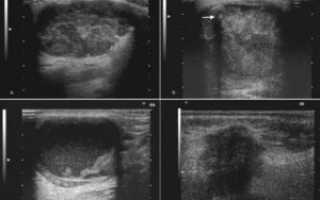

Результаты исследования ушей показывают все изменения, которые происходят в структуре тканей. Диагностика помогает установить точную локализацию воспалительного очага, определяет наличие полипов или новообразований и их размеры.